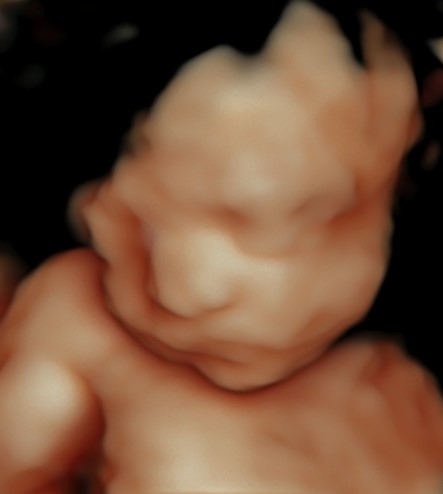

4D/5D/HD Ultrasound Gallery

Gallery